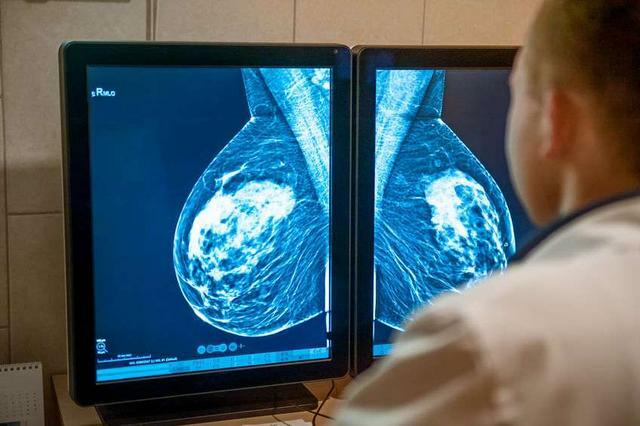

3、乳腺增生、乳腺癌

這一原因要引起足夠的重視。女性如果經常有胸痛的症狀,可以用手觸摸一下乳房的位置,感受一下其中是不是有腫塊,乳腺增生、乳腺癌都會表現為乳房內的腫塊。

其中,乳腺增生引起的腫塊邊緣清晰,質地比較柔韌、有彈性,但乳腺癌則不同,乳腺癌的腫塊質地堅硬,邊緣模糊,難以推動,而且還有凹凸不平的感覺。

如果發現有腫塊的,一定要及時到醫院進一步檢查,並針對檢查結果作出相應的處理。